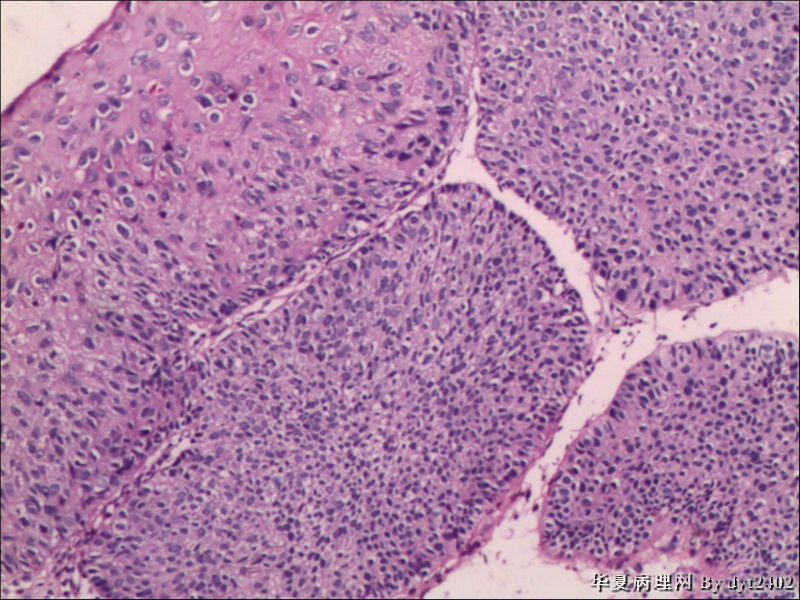

• 宫颈活检 其中一点较迷糊图3

图3

四点中三点是CIN iii,另一点怀疑有更重病变

这个病人是44岁,去年11月底阴道脱落细胞、TCT均见细胞异常,建议活检,病人犹豫,接着单位组织到外院体检时做阴道镜正常,后霉菌感染,此时宫颈未涂醋肉眼看还光滑,直至今年3月来做活检,事前做白带检查又见异常细胞,宫颈未涂醋见后上唇白上皮,涂醋酸后上下唇都有厚白上皮,镶嵌,夹活时上皮剥脱,未能夹到间质,阴道镜医生说至少有CIN III 到原位癌了。。镜下其中3点CIN III无疑,唯有9点处如6、7、11、14等所示结构,但我未见间质浸润,不能说是浸润癌,不知道有没基底细胞样鳞癌的可能,我发了个原位癌不除外深部有更重病变,。